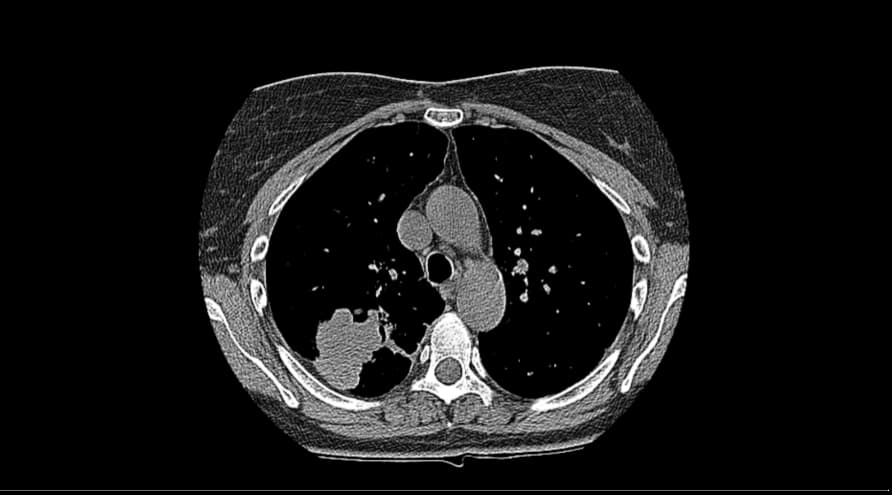

打开单张DICOM图像,如下图所示。